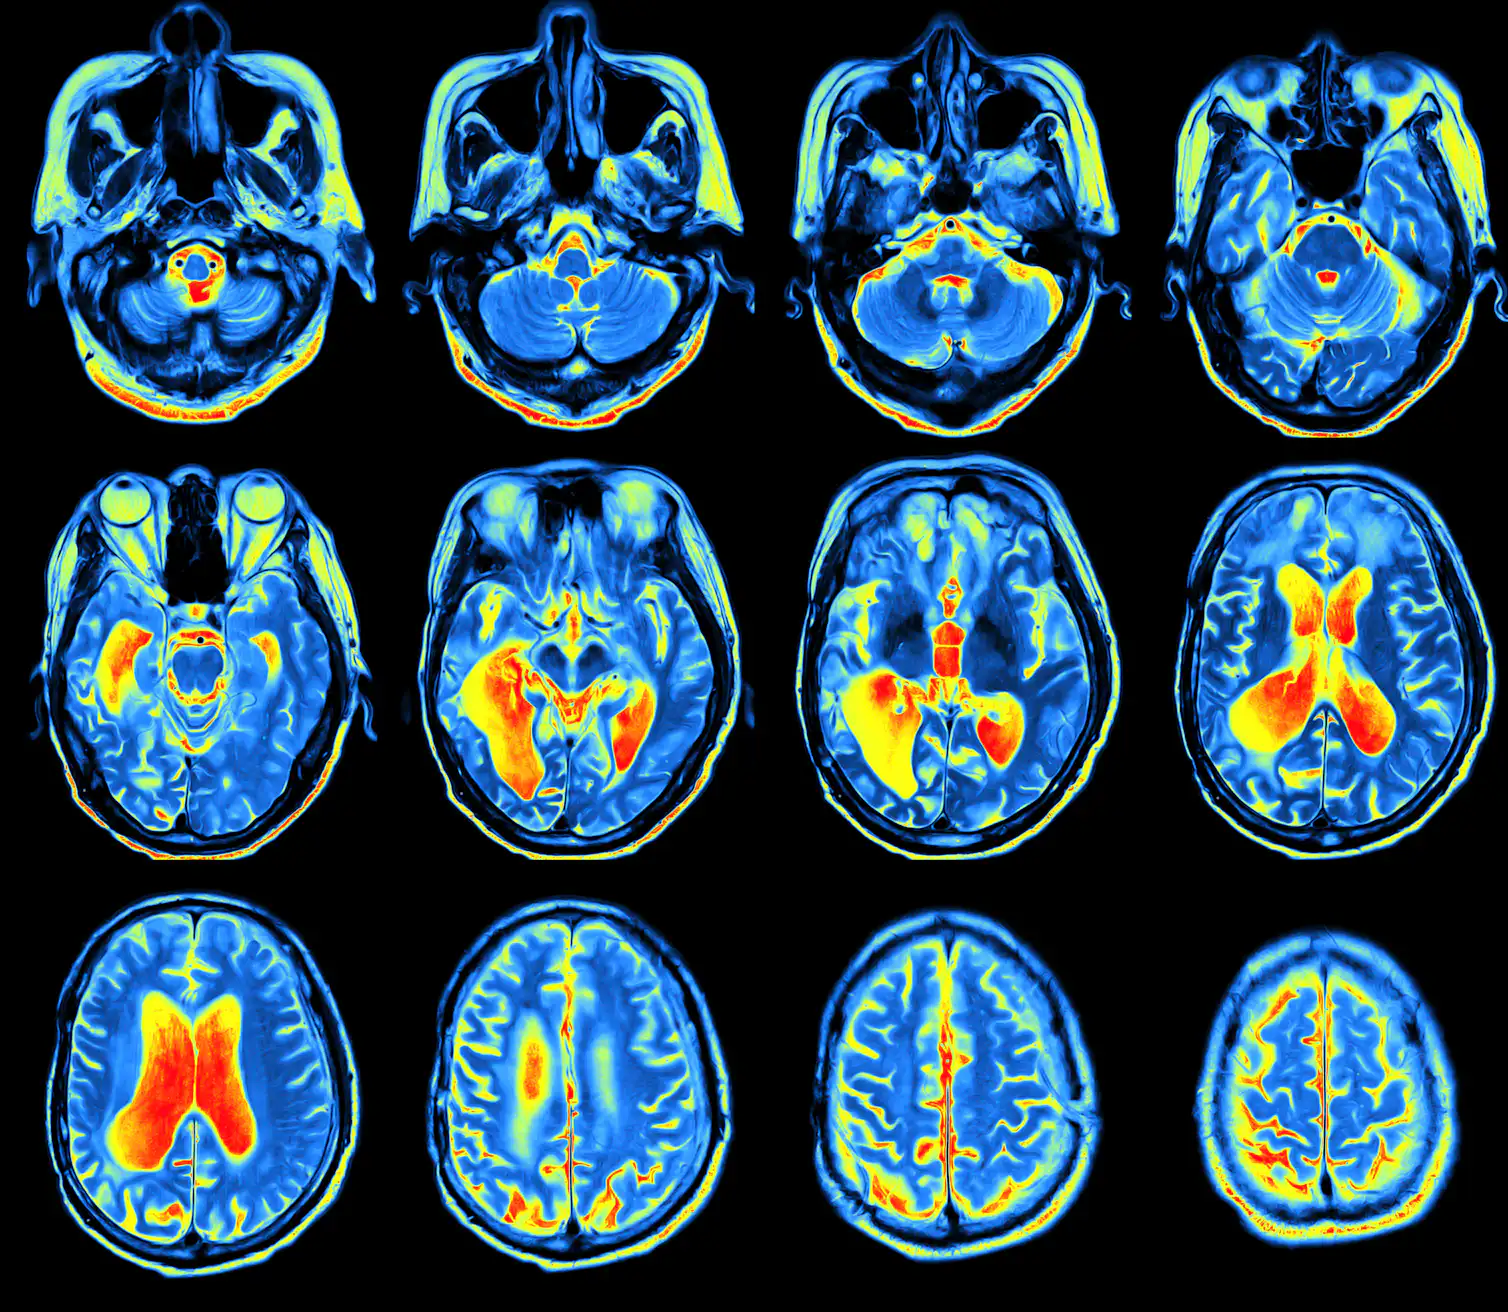

تظهر عمليات مسح الدماغ أن "شبكة القراءة" هذه جلية (واضحة) في نفس المكان في الدماغ في كل شخص. تتشكل شبكة القراءة هذه عندما نتعلم القراءة وتقوي الروابط بين مناطق اللغة والكلام في الدماغ (٧) ، وكذلك المنطقة التي أصبحت تُعرف باسم "منطقة شكل الكلمة المرئية"“visual word form area” وتختصر ب VWFA (٨).

التصميم لبناء الدوائر circuitry الأساسية مرمز / مشفر بشكل ما في جينوماتنا. أي ان الجينوم البشري يشفر مجموعة من القواعد النمائية التي ، عندما تتطور، ستفضي الى الشبكة.

| القراءة تغير الدماغ حرفياً |